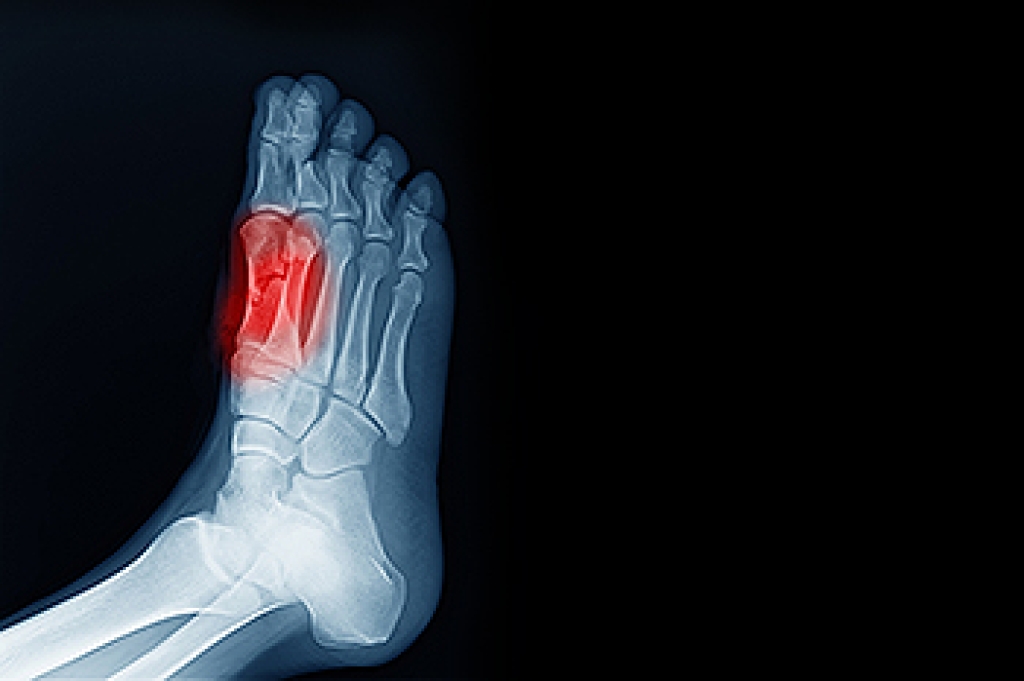

There are various types of injuries that can affect the Achilles tendon. The two most common injuries are Achilles tendinitis and ruptures of the tendon.

- Extreme pain and swelling in the foot

Achilles tendon injuries are diagnosed by a thorough physical evaluation, which can include an MRI. Treatment involves rest, physical therapy, and in some cases, surgery. However, various preventative measures can be taken to avoid these injuries, such as: